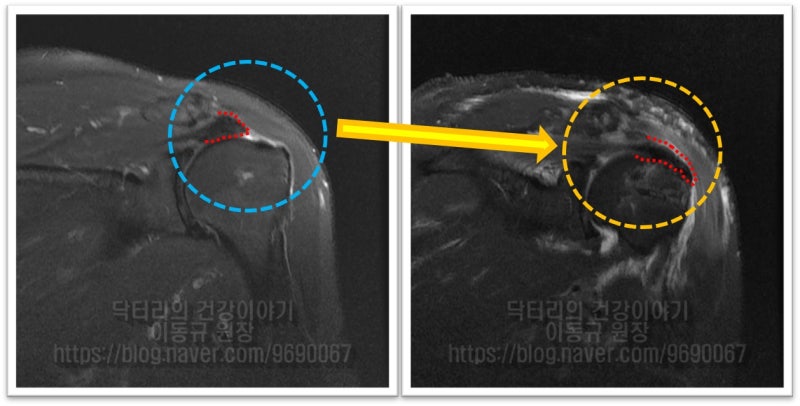

수술 후 MRI 를 비교해 보겠습니다.

이열 봉합법으로 봉합을 하게 되면 1. 보다 많은 파열된 회전근개가 부착될 상완골에 넓은 면적으로 부착될 수 있고. 2. 더 단단히 봉합됨으로써 회전근개에 걸리는 장력을 더 견딜수 있게 되며, 3. 단단히 봉합되었기 때문에 재활을 더 빨리, 편하게 진행할 수 있게 됩니다. 67세의 나이에도 현재 아주 열심히 재활하고 계시고 이제는 밤에도 잘 자고 생활도 잘 하신다고 좋아라 하셨습니다. 개인적으로는 회전근개 파열의 거의 모든 수술에 이열 봉합법을 이용하여 봉합을 합니다. 상기의 이유로 단단히 봉합할 수 있고 초기재활을 빨리 할 수 있기 때문입니다.